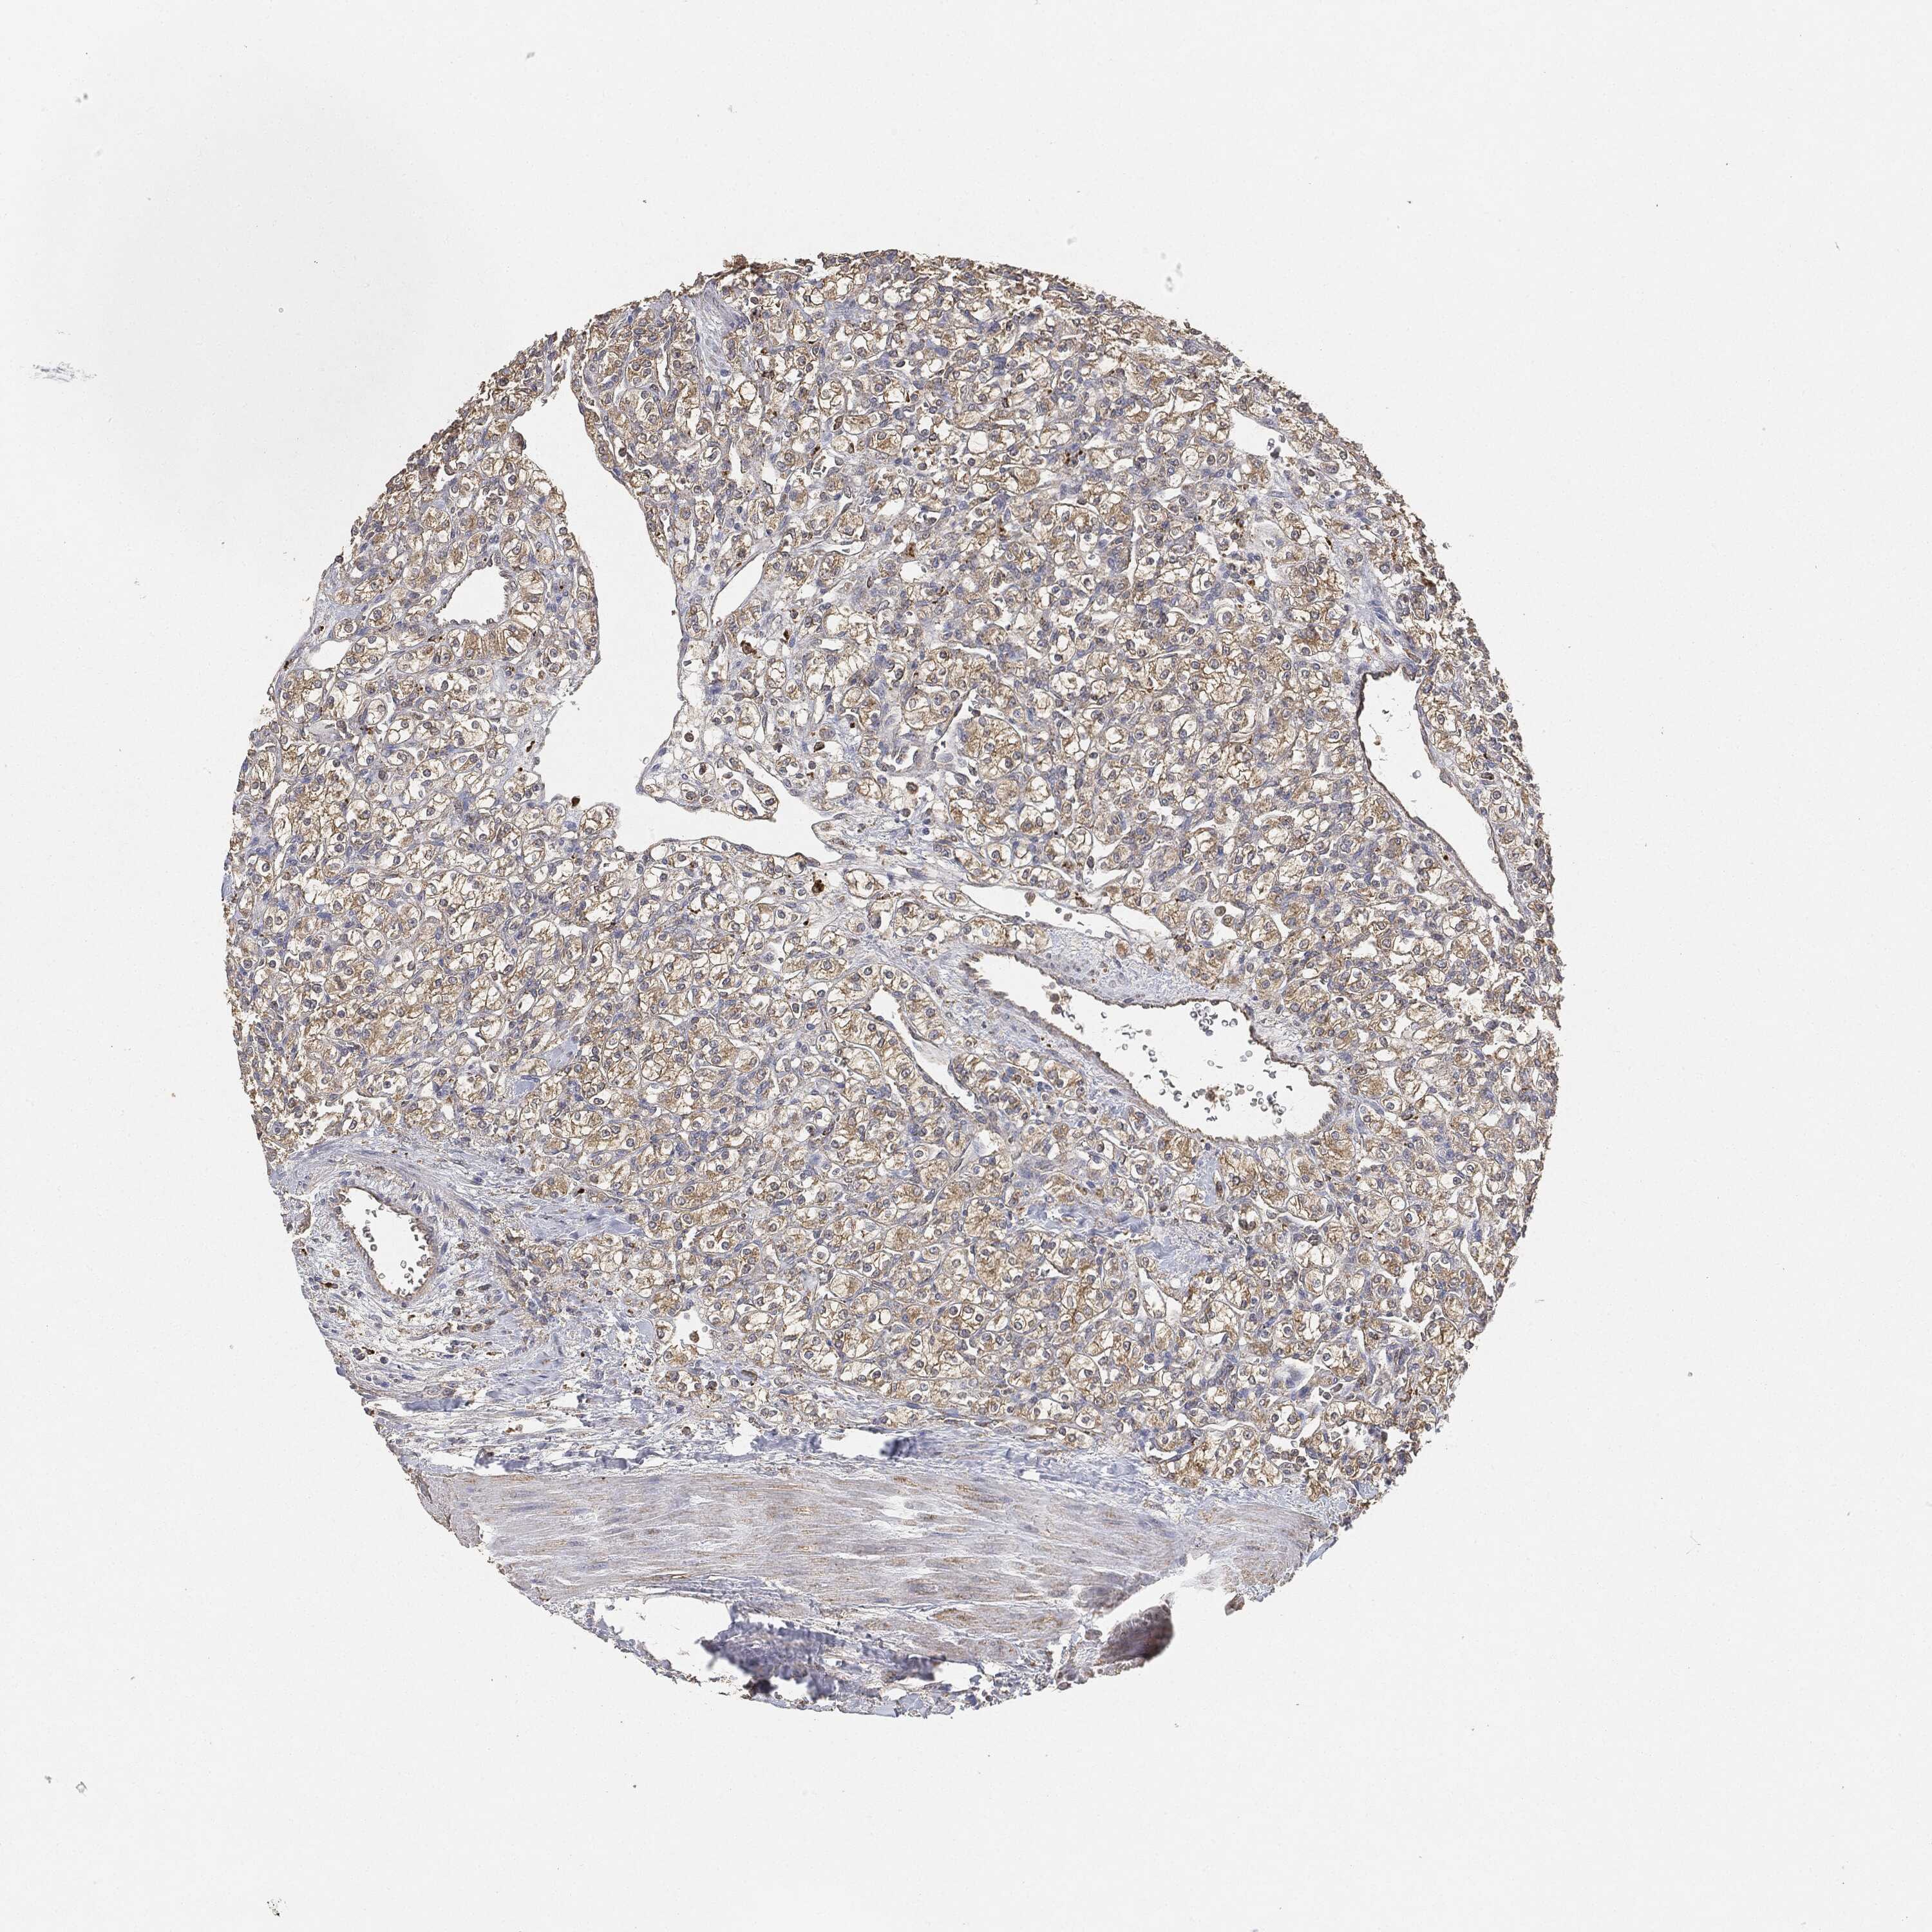

CANCER RENAL CANCER Show tissue menu

KICH TCGA KIRC TCGA KIRC VALIDATION KIRP TCGA PROTEIN RCC CPTAC PROTEIN EXPRESSION